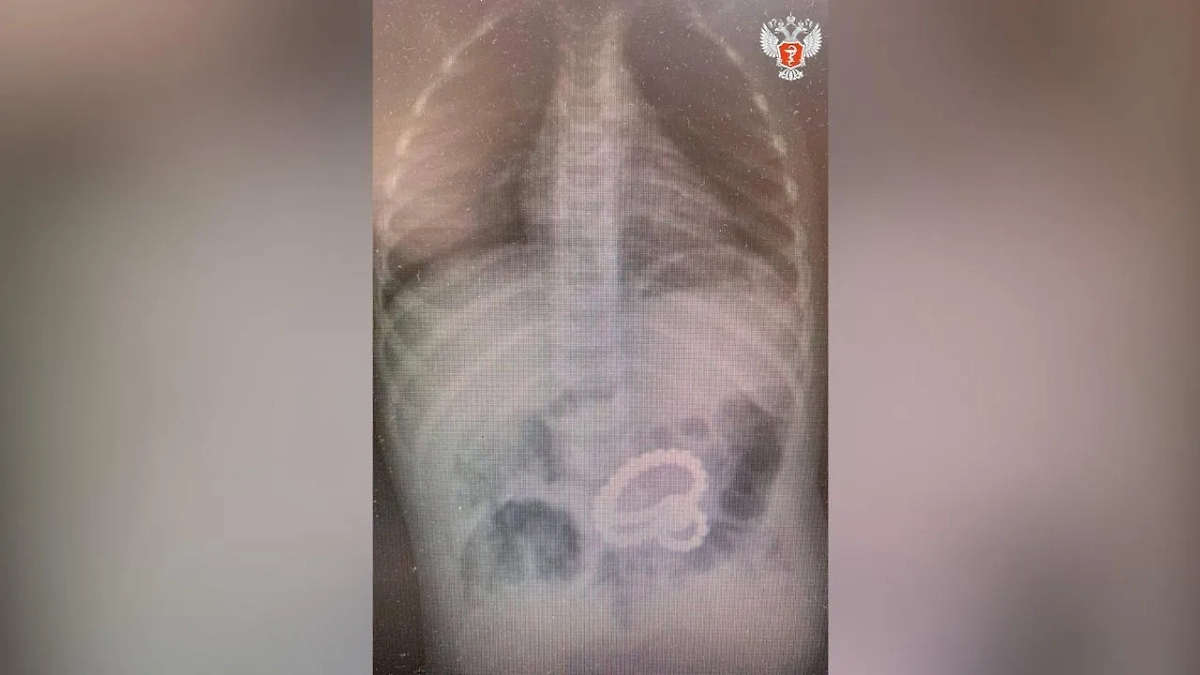

Магниты в желудке мальчика. Фото © Telegram / Минздрав России

«Мы провели гастроскопию, в ходе которой последовательно извлекли 45 магнитов и металлический шарик из желудка», — поделился подробностями операции завэндоскопического отделения Александр Климов.

В ходе операции выяснилось, что три магнита уже переместились в кишечник, а их извлечение требовало хирургического вмешательства. Как пояснили врачи, ребёнок глотал магниты в разное время, что привело к их сцеплению через стенки желудка и кишечника. Оставшиеся магниты были удалены через миниатюрный разрез в брюшной стенке. После успешной операции малыша выписали под амбулаторное наблюдение.